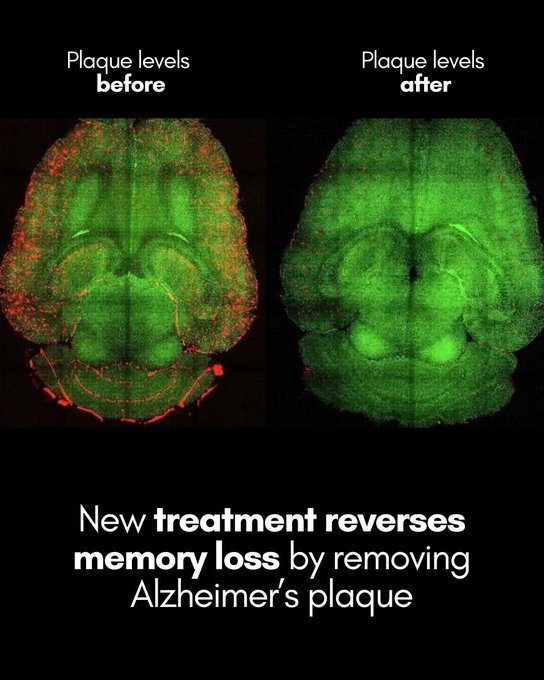

![Massimo (@rainmaker1973) on Twitter photo Korean researchers developed a new technology to treat cancer cells by reverting them to normal cells without killing them.

[Gong, J., et al. (2024). Control of Cellular Differentiation Trajectories for Cancer Reversion. Advanced Science. doi. org/10.1002/advs.202402132] Korean researchers developed a new technology to treat cancer cells by reverting them to normal cells without killing them.

[Gong, J., et al. (2024). Control of Cellular Differentiation Trajectories for Cancer Reversion. Advanced Science. doi. org/10.1002/advs.202402132]](https://pbs.twimg.com/media/G_lv_8xXIAAN43F.png)